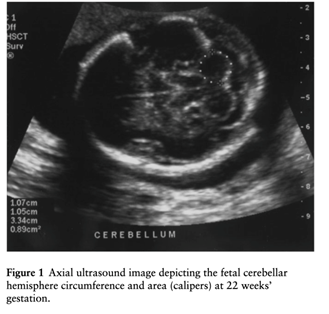

Sherer et al., Nomograms of the axial fetal cerebellar hemisphere circumference and area throughout gestation, Ultrasound Obstet Gynecol 2007; 29: 32 – 37

Beispiel Zerebellärer Hemisphärenumfang

Tabelle Zerebellärer Hemisphärenumfang

Tabelle Zerebelläre Hemisphärenfläche